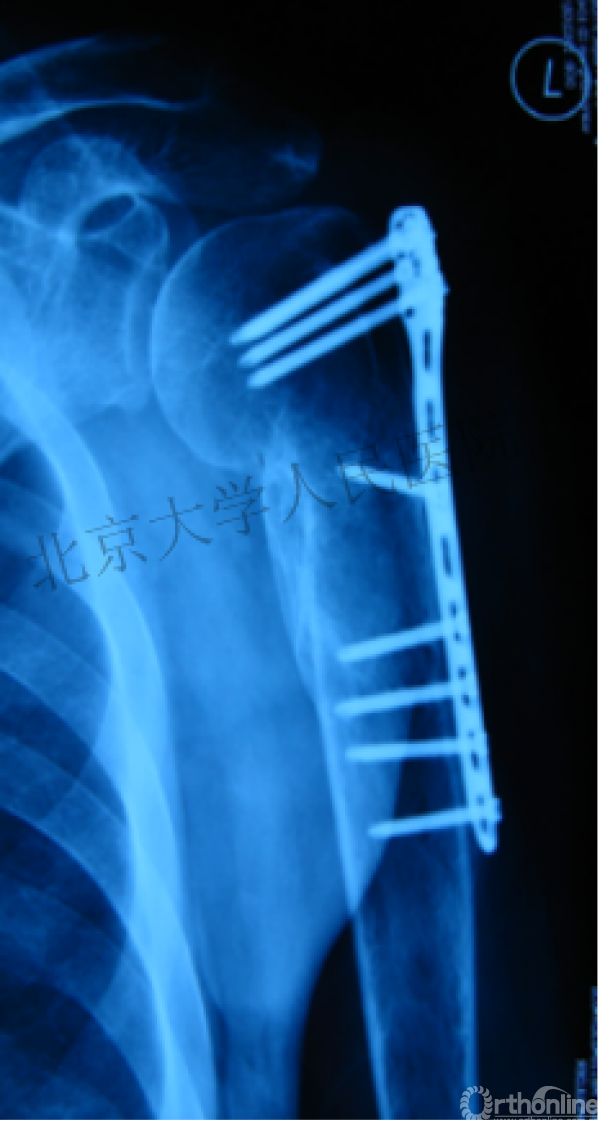

另一个留有遗憾的病例,您的选择?PHN?

临床中的广泛内固定治疗不断地提出思考

结构力学上抗折断能力髓内钉明显强于钢板

三、其实应用肱骨近端髓内钉治疗肱骨近端骨折有时有许多优势。

作为髓内固定,抗轴向压力较偏心固定的钢板强。